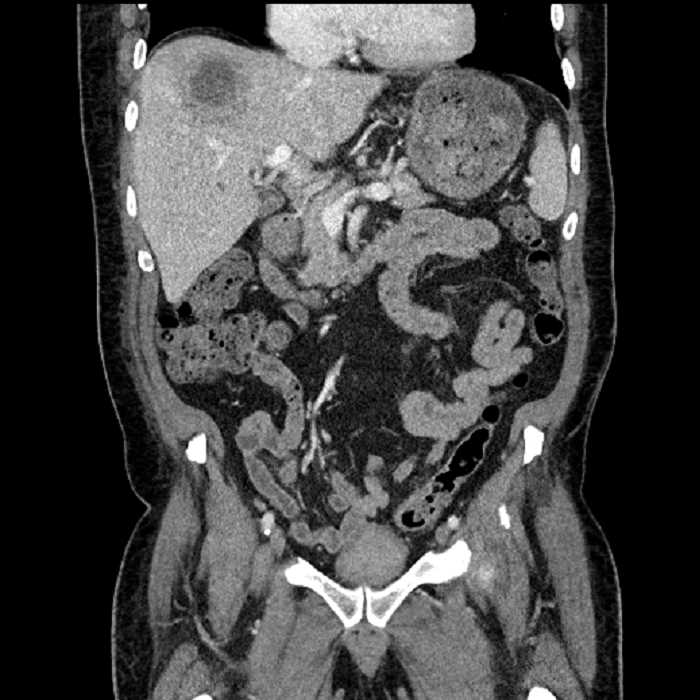

Age: 63

Sex: Male

Indication: Abdominal pain

• Large fluid density structure in hepatic segments 7 and 8 measuring 10 x 7 x 7 cm with internal septation and circumferential ill-defined low density compatible with edema

• Peripherally enhancing subcapsular collections along the anterior margin of the left hepatic lobe measuring 3 x 1 cm and 2 x 1 cm

• Hepatic abscess

Acute sigmoid diverticulitis complicated by a small contained perforation and a large abscess in the right hepatic lobe. Additional small subcapsular abscesses along the anterior margin of the left hepatic lobe.

• The classic CT imaging appearance is a double target sign with internal low density surrounded by an internal enhancing rim (capsule) and a low density external rim (edema)

Hepatic abscess showing the double target sign with low density internally surrounded by a thin inner enhancing rim (red arrow) and ill-defined outer low density rim (yellow arrow). Blue arrow indicates an internal septation. Red arrows: additional smaller subcapsular abscesses. Red arrow: focal contained perforation associated with diverticulitis.